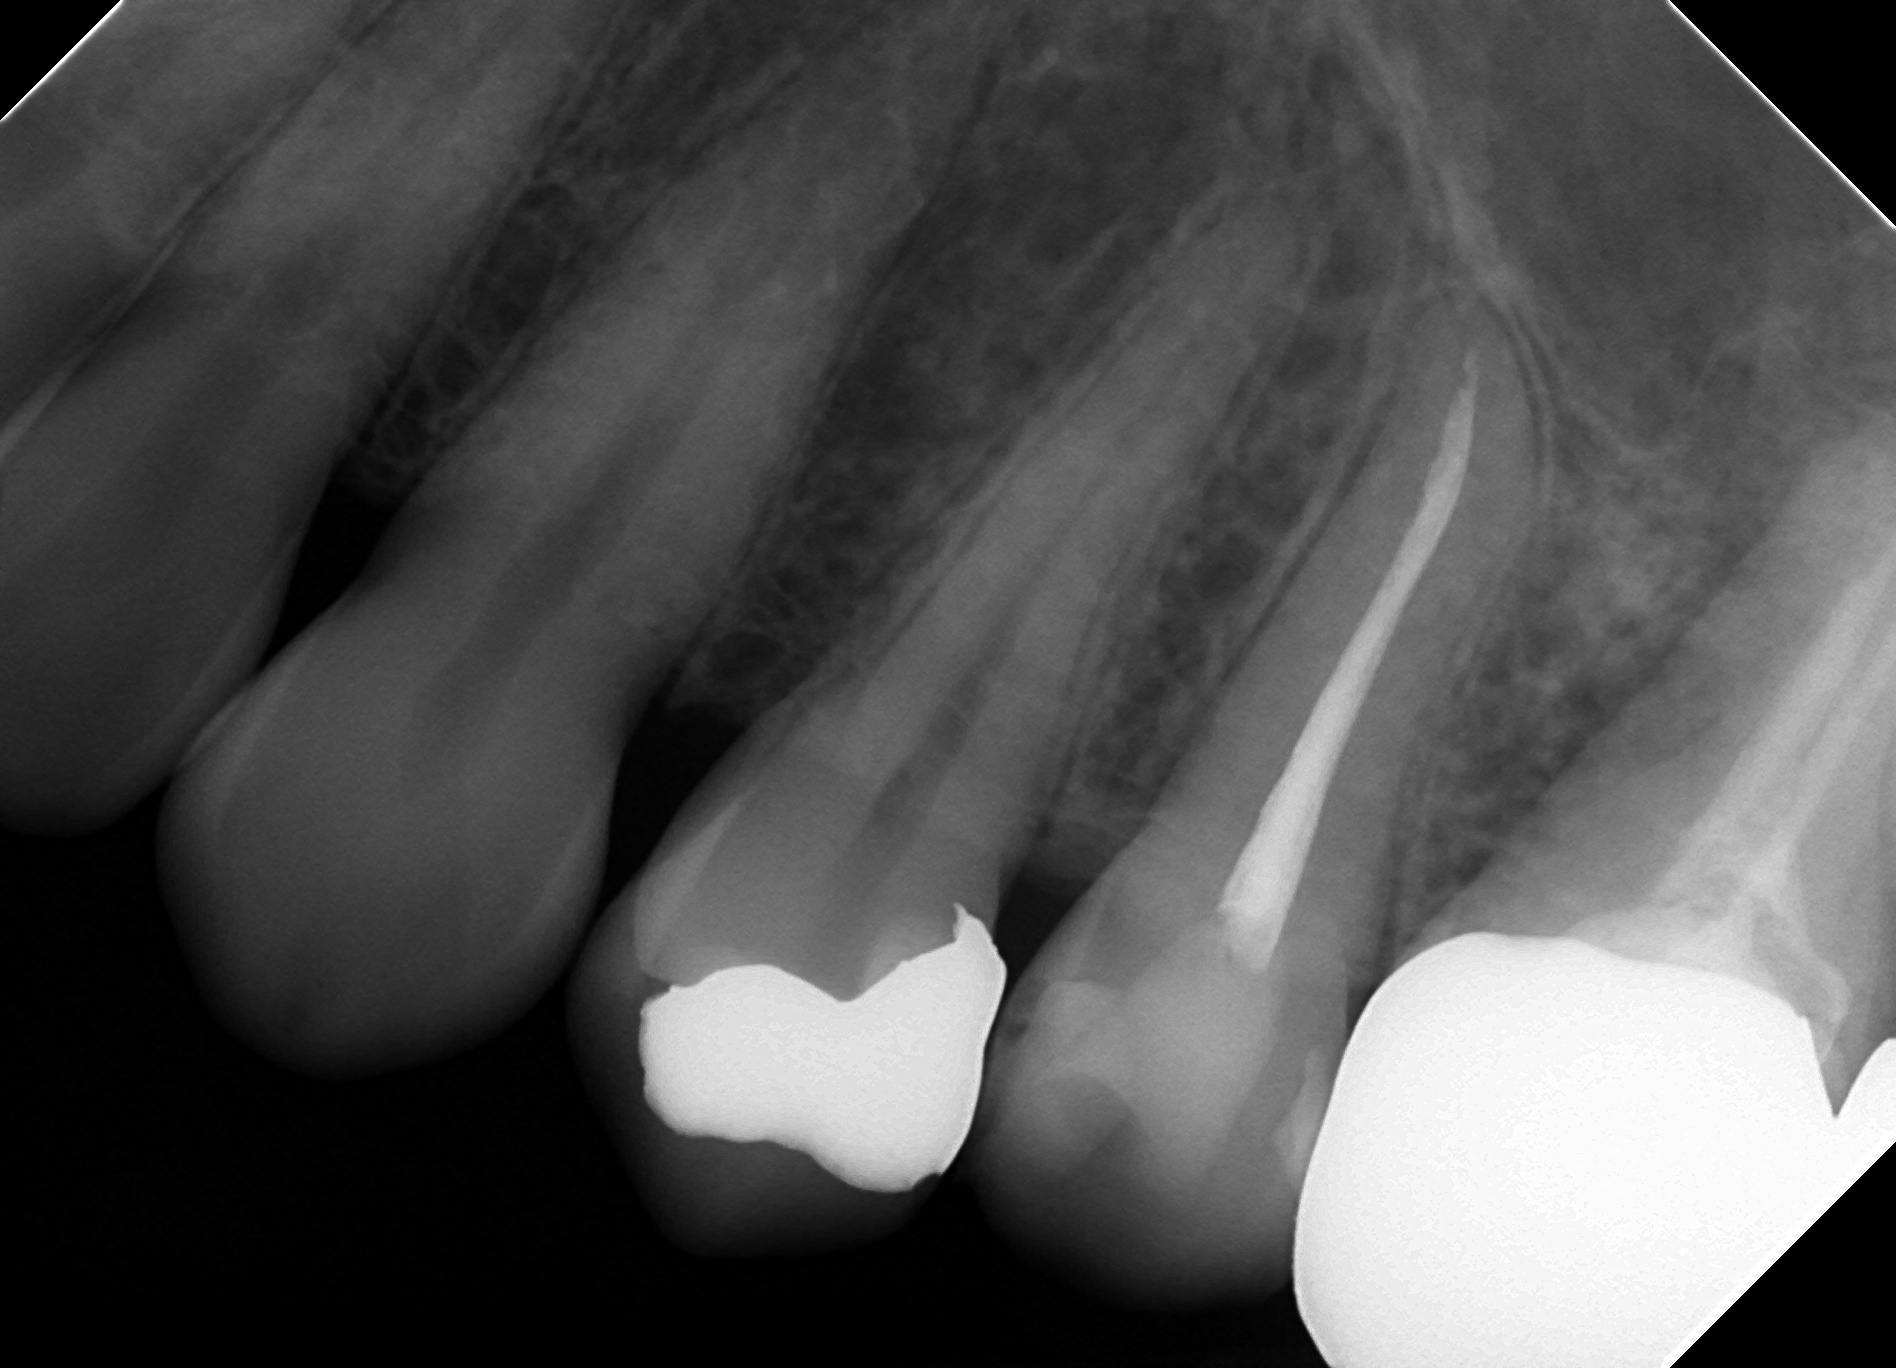

「歯の神経をとる」という行為

今回は虫歯が大きく歯が痛んでしまった人が行う「歯の神経をとる」という行為がどんな手順で行われているかを動画を撮影したので解説しながら説明していきたいと思います。 【~1分まで】 歯の神経の部分まで削っています 【1分~1 […]